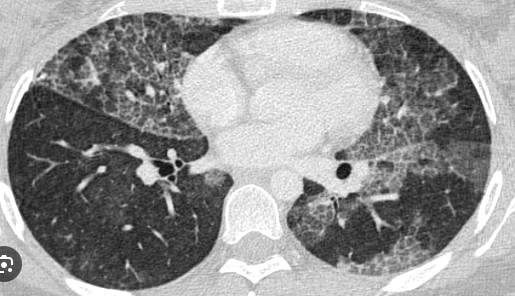

¿Para qué sirve la TAC en neumonía?

A

• Se ven diferentes patrones que nos orientan a un microorganismo en particular

• Vidrio esmerilado o patrón empedrado